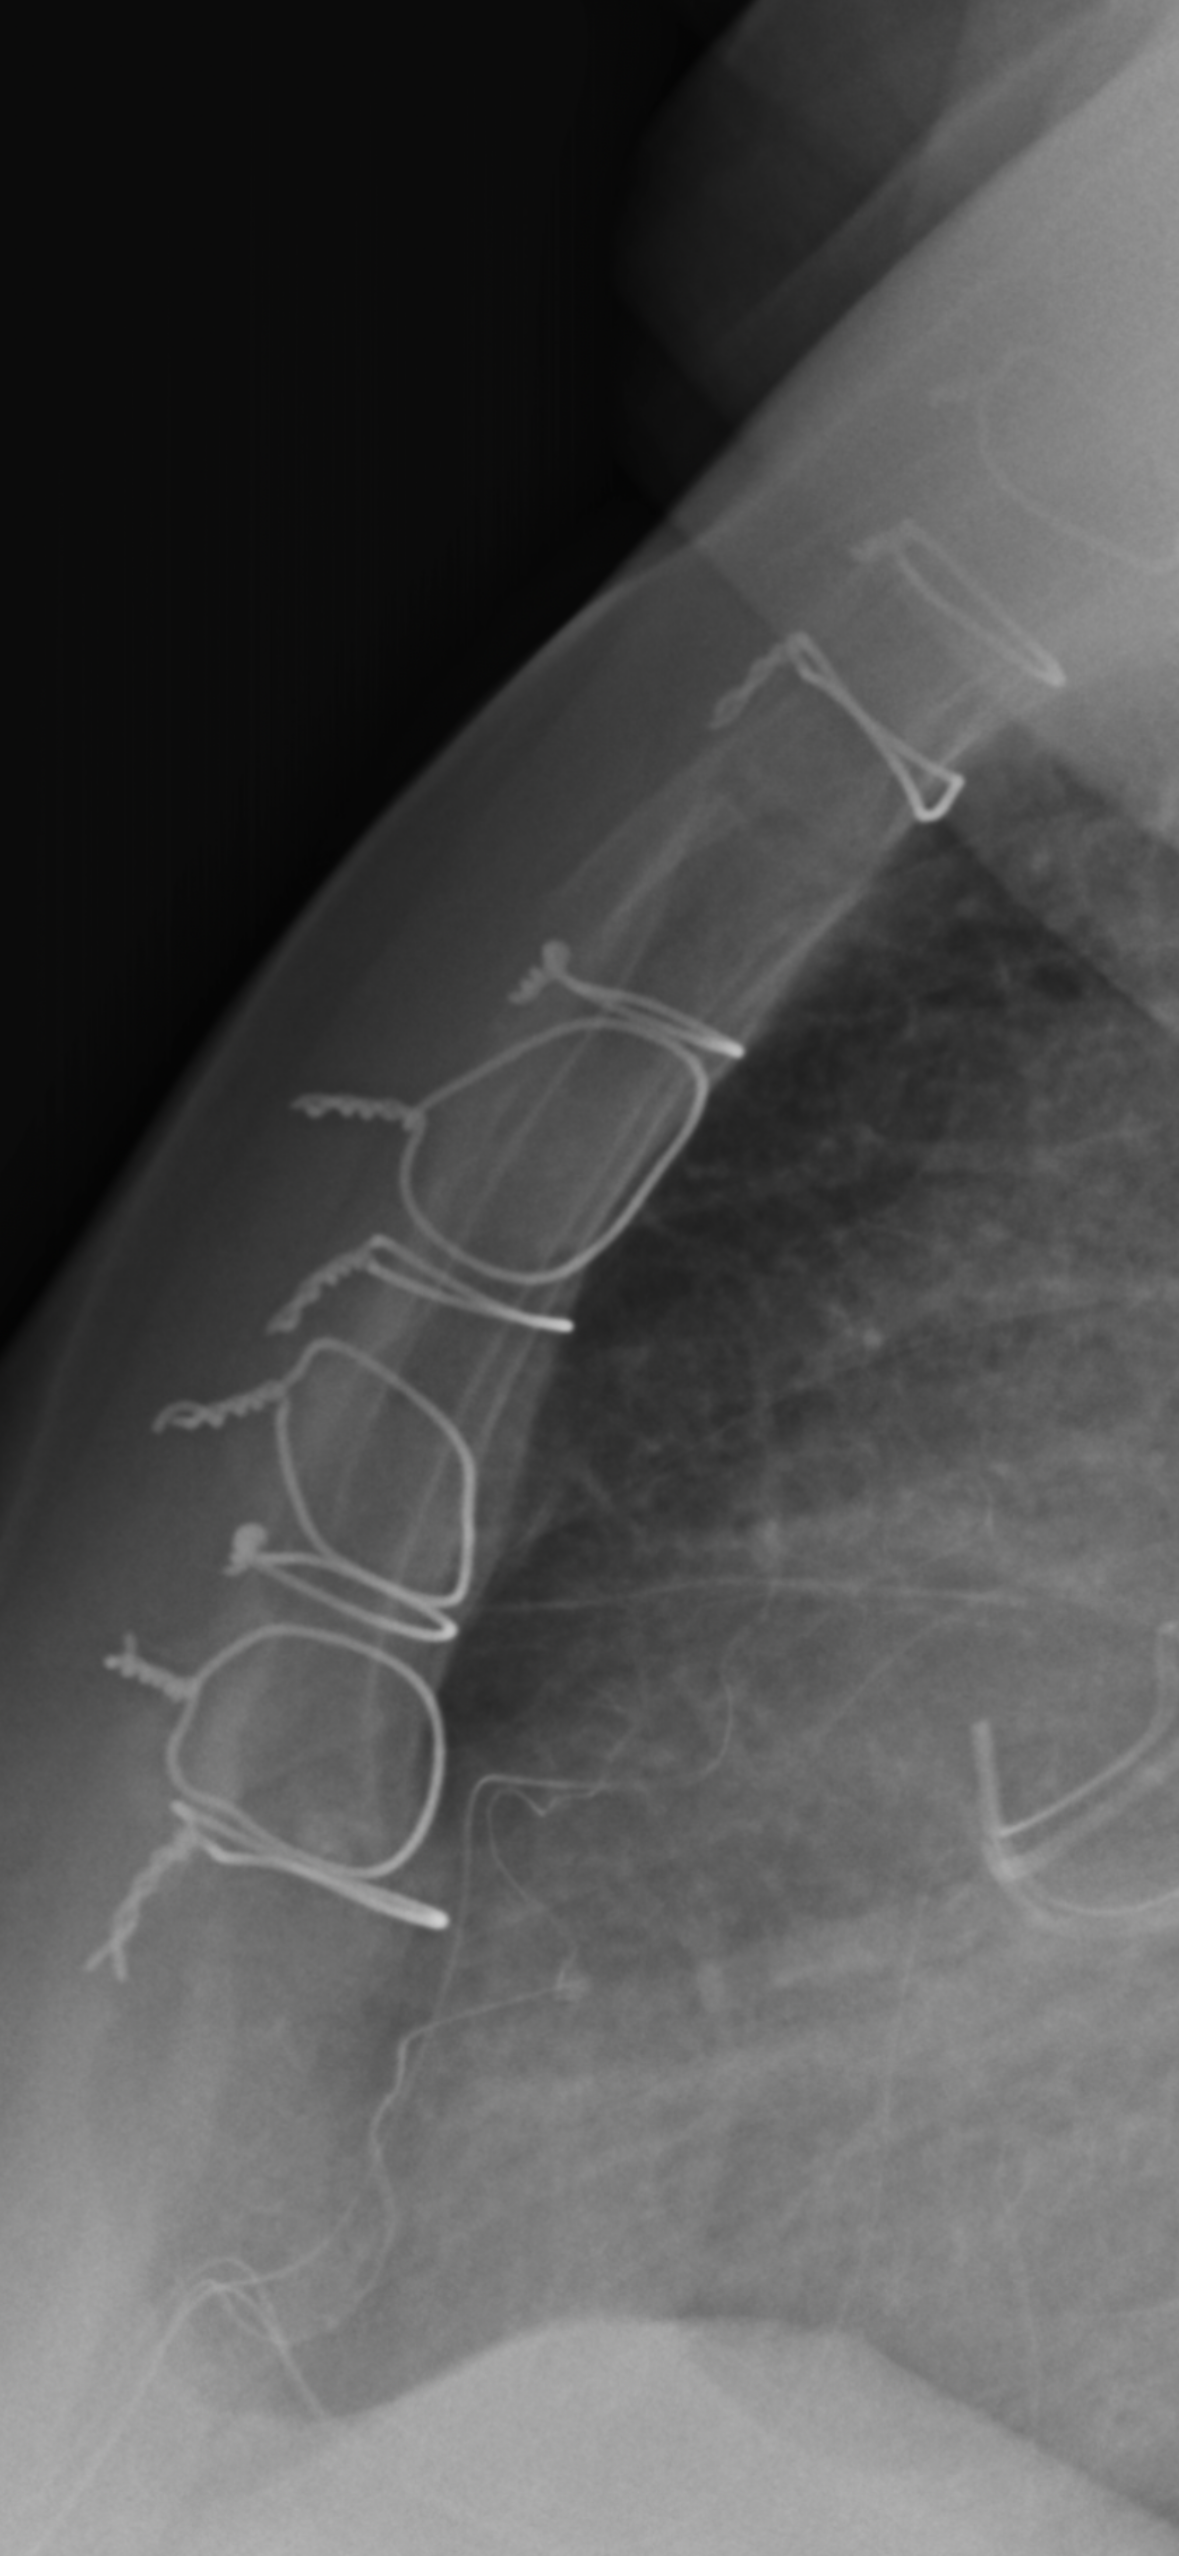

Marie Myers Yes, those wires are deep into your sternum. I am sure you are uncomfortable…

Richard Munson Wow, those look like clothes hanger wires.

Grace Mason Thanks for sharing pic of your wire Deb. It's interesting to see the size of it and the twist. I'm am ... Read more

Grace Mason Thanks for sharing pic of your wire Deb. It's interesting to see the size of it and the twist. I'm amazed I don't "feel" them all the time, though I do have occasional twinges that I imagine have something to do with my wires.

Pamela Gregory Wow!!! That is crazy how primitive it looks